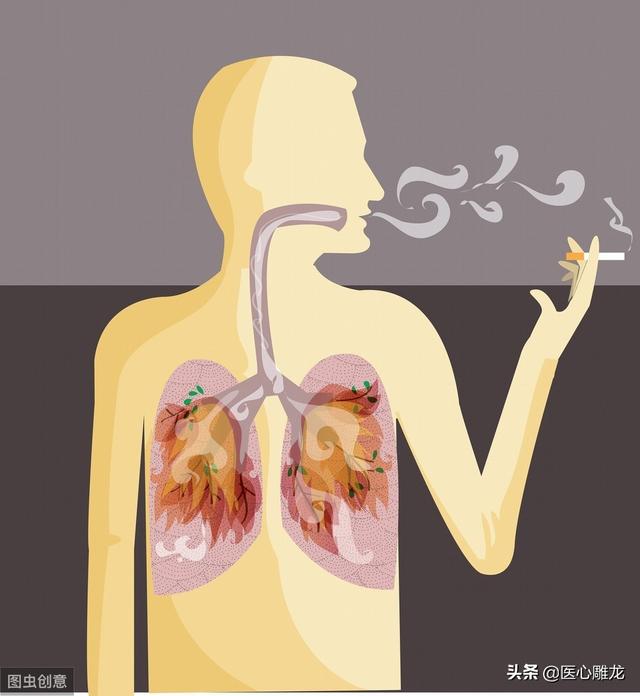

もちろん、これらの要因とは別に、スナッフ・スモーキング、アルコール中毒、肥満なども胃がんに関係している。

- 喫煙、飲酒、夜更かしなどの悪い習慣;

3.カップルは深夜のスナックに熱心で、一緒にタバコを吸い、酒を飲み、一緒にカラフルなナイトライフを過ごし、一緒に様々な社会活動に熱心である。

理由1:受動喫煙が原因

臨床上、夫婦同時に肺がんと診断されるケースは多く、夫が喫煙し、妻が副流煙を吸引することが重要な原因の一つとなっている。 煙の害について語るつもりはなく、タバコは肺がんや胃がんなど十数種類のがんを引き起こすという研究結果もあり、副流煙は副流煙以上に有害であるという研究結果もあるため、喫煙は夫婦そろってがんになる重要な原因となっている。